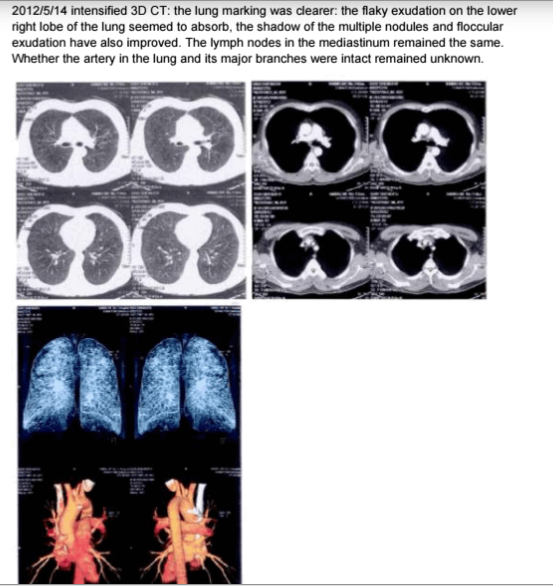

Caso 3

45 años. Tos y fiebre durante +15 días.

Diagnóstico: neumonía severa y daño pulmonar.

👇 ImageImageImageImage